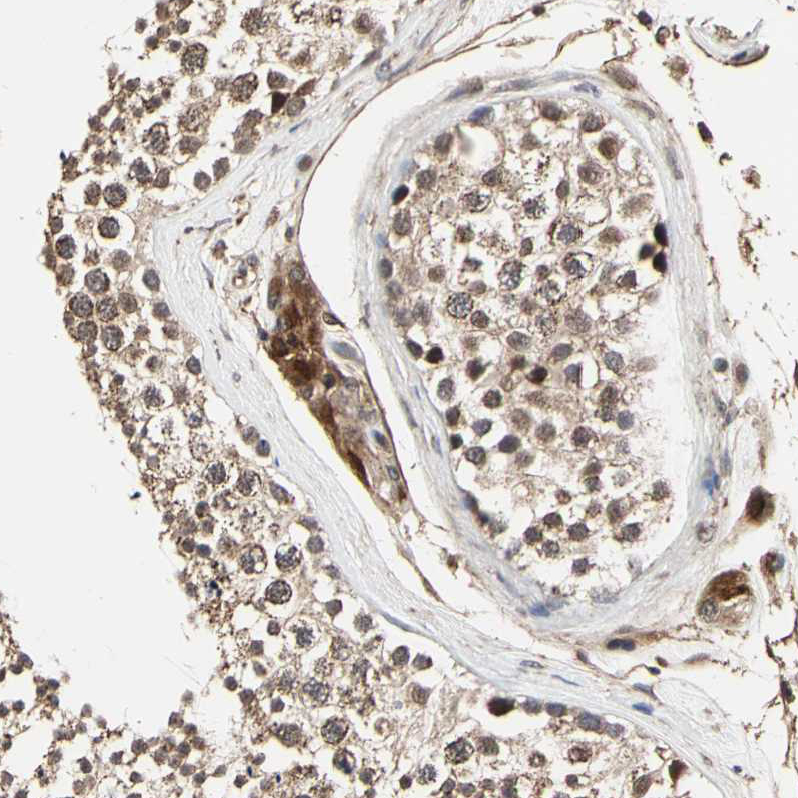

Immunohistochemical staining of human cerebral cortex shows strong cytoplasmic positivity in neurons.